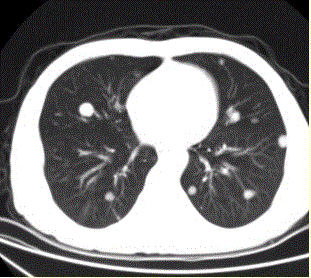

问题 患者男,45岁,因肝硬化、肝癌行肝移植术后6个月,咳嗽2周,来院复查。CR及CT影像如下图。 对于该病例,首选诊断为

选项 A.肺结核 B.肺转移瘤 C.肉芽肿性疾病 D.支气管肺泡癌 E.淋巴瘤 F.支气管肺癌

答案 B

解析 B